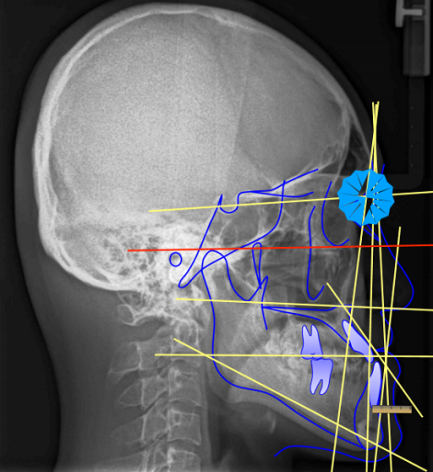

除了症状,医生也会借助X光、温度刺激等方法辅助诊断。

杀死牙神经听起来很吓人,其实就是平常所说的根管治疗,大概过程是打开牙髓腔,取出坏死的牙髓,清洗消毒根管内部,然后将特殊的材料填充进去。彻底没了牙髓,也就不会再出现牙髓发炎的情况了。